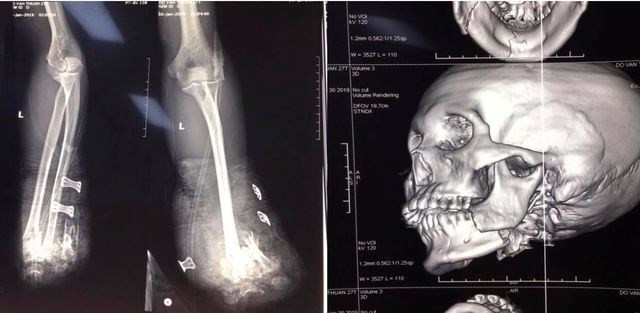

Gần 300 trường hợp nhập viện cấp cứu do tai nạn pháo nổ ảnh 1Hình ảnh chụp X-quang về tai nạn thương tích của một bệnh nhân bị tai nạn do pháo nổ tại Bệnh viện Trung ương Quân đội 108. (Ảnh: PV/Vietnam+)

Tối 29/1, các bác sỹ Khoa Cấp cứu (Bệnh viện Trung ương Quân đội 108) đã tiếp nhận bệnh nhân Đỗ Văn T. (25 tuổi, ở Hải Phòng) chuyển đến viện trong tình trạng cụt 2 bàn tay, vết thương vùng hàm mặt, chảy nhiều máu vì tai nạn do pháo nổ tự chế./.